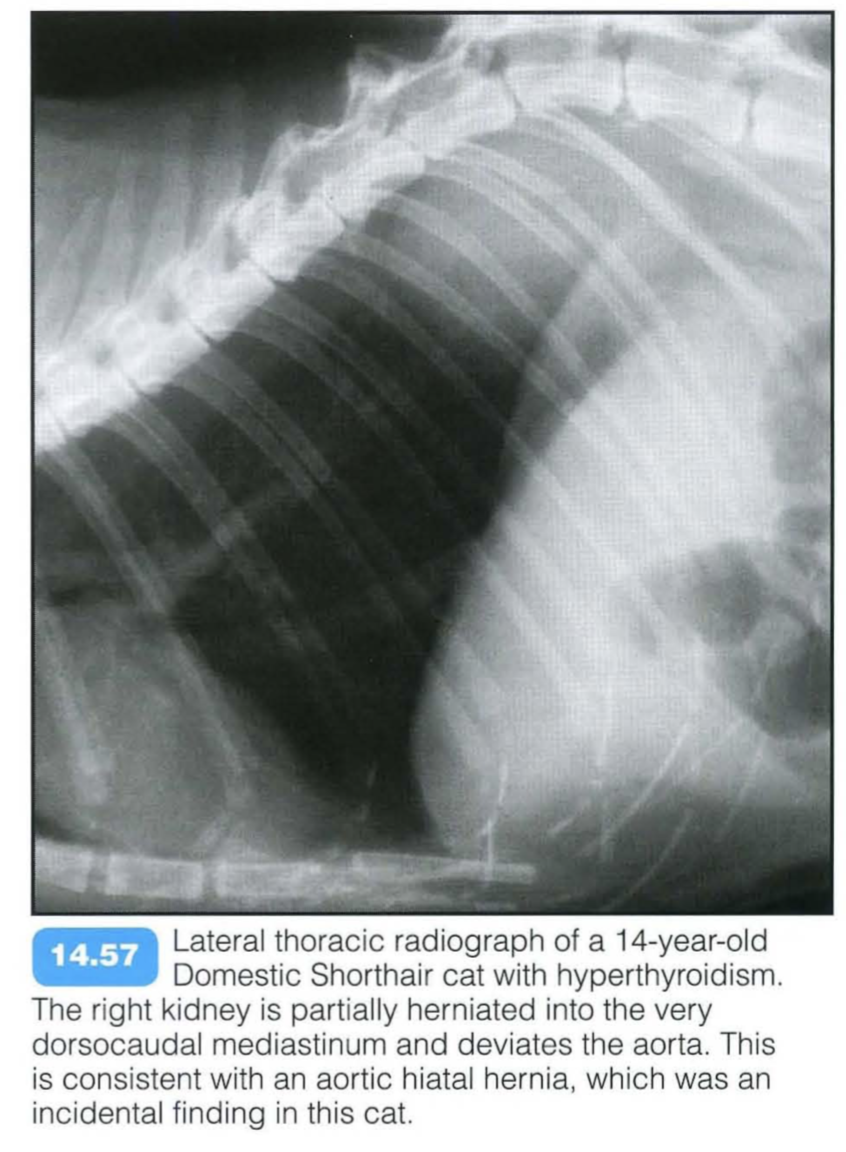

Aortic hilar hernia

The aortic hilus is the only diaphragmatic opening that connects the mediastinum with the retroperitoneal space. Free mediastinal gas can pass through the hilus and enter the retroperitoneal space relatively easily. If defects in this hilus exist, retroperitoneal organs such as the adrenal glands and kidneys can prolapse into the mediastinum. Intramediastinal kidneys are rare in dogs and cats and are usually detected incidentally.

Radiographic findings include: